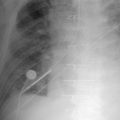

Central Venous Lines ( Figs. 22-1 to 22-13 )

To avoid mechanical irritation (from the catheter tip) and chemical irritation (from infusate) of the right atrium, the catheter tip of a central venous line should be further than the junction of the internal jugular vein and subclavian veins (near the level of the first thoracic rib). In addition, the tip should not be further in than the junction of the superior vena cava and right atrium. Central venous catheters that are intended to record central venous pressure should lie distal to the last venous valves (in the subclavian and internal jugular veins, 2.5 cm proximal to the beginning of the brachiocephalic vein) and before the right atrium. The ideal position of the tip of a peripherally inserted central catheter (PICC) line is in the distal superior vena cava.